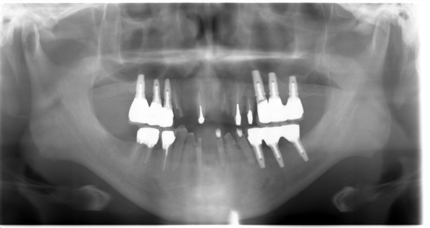

受傷時パノラマレントゲン(2018年5月17日)

【受傷時 パノラマレントゲン】

【最終補綴物装着 パノラマレントゲン】